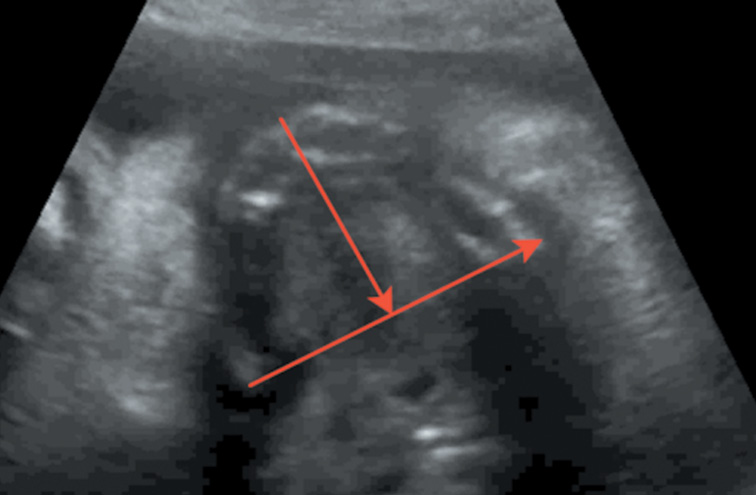

Измерение соотношения ширины нижней челюсти и ширины верхней челюсти производилось в осевом положении на уровне альвеолярного отростка 10 мм кзади от передней костной границы (рис. 5, 6). Среднее значение этого коэффициента равно 1,02 ± 0,12 (SD), следовательно, коэффициент меньше 0,78.

Рис. 5. Длина нижней челюсти / Fig. 5. Length of the lower jaw

Рис. 6. Длина верхней челюсти / Fig. 6. Length of the upper jaw

Оценка развития челюстей также оценивалась по длине нижней челюсти — длина нижней челюсти в соотношении с биометрией плода (длиной бедренной кости). При измерении длины нижней челюсти проксимальным ориентиром становился височно-нижнечелюстной сустав. Увеличение длины нижней челюсти соотносится с увеличением срока гестации от 20 мм в 20 недель до 37 мм в 28 недель.

Челюстной индекс рассчитывался после измерения переднезаднего диаметра нижней челюсти плода в осевой плоскости в соотношении с бипариетальным размером (рис. 7). Данный индекс не зависел от срока гестации.

Рис. 7. Переднезадний диаметр нижней челюсти плода / Fig. 7. Anteroposterior diameter of the lower jaw of the fetus